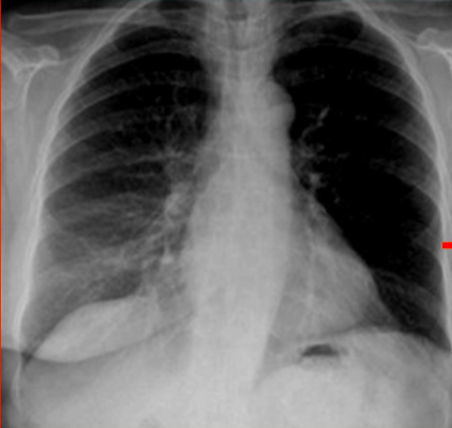

X-Ray Images

Fleischner sign (enlarged pulmonary artery)

- sensitivity: ~14%

- specificity: ~92%

- positive predictive value: ~38%

- negative predictive value: ~76%

- sensitivity: ~22%

- specificity: ~82%

- positive predictive value: ~29%